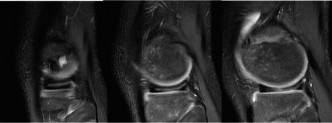

The patient responds well to a period of nonoperative management and returns to sporting activity. He is playing basketball when he has acute onset of pain, swelling, and decreased range of motion after an awkward landing. Plain radiographs are unremarkable, and a repeat MRI (Fig. 10–25) is obtained.

Figure 10–25

The correct answer is (D). The patient has an unstable lesion on MRI which is acute; therefore every attempt should be made to salvage the lesion. The ideal treatment would be fixation of the lesion although the determination for treatment cannot be made until it is examined arthroscopically. If the lesion is not deemed stable during arthroscopy, then drilling would be a reasonable option (and can be combined with fixation). If the fragment is nonviable, microfracture would be a reasonable option to stimulate fibrocartilage formation as long as the donor site is not too large. Fragment removal and chondroplasty is not ideal for a young patient; particularly one who is engaged in sporting activities. Every attempt should be made to salvage the lesion and/or stimulate new cartilage formation if the fragment is unsalvageable. The lesion is shown arthroscopically (Fig. 10–26). The appropriate treatment option is:

Figure 10–26

The correct answer is (A). The patient has an unstable lesion on MRI and is demonstrating instability on arthroscopic examination. The fragment is viable therefore fixation of the lesion is optimal. Drilling would be appropriate for a stable lesion but both imaging and clinical findings suggest instability. As the lesion is viable, it should not be removed. Therefore, microfracture and mosaicplasty in the absence of exposed subchondral bone should not be utilized. Objectives: Did you learn...? The clinical presentation and physical examination findings of OCD lesions of the knee?